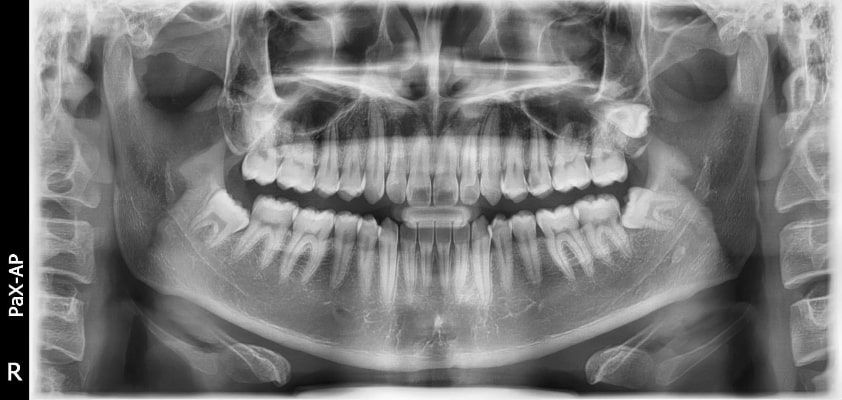

El innovador FOV proporciona un volumen en forma de arco que muestra una vista más amplia de la dentición en comparación con otros dispositivos del mismo FOV.

Normalmente, una imagen de 10x8.5 muestra el diente No.8. Sin embargo, cuando los terceros molares están tumbados sobre su lado hay una gran posibilidad de que el diente se corte de la imagen.

El “volumen en forma de arco” elimina esta posibilidad y muestra el área de dentición oculto.